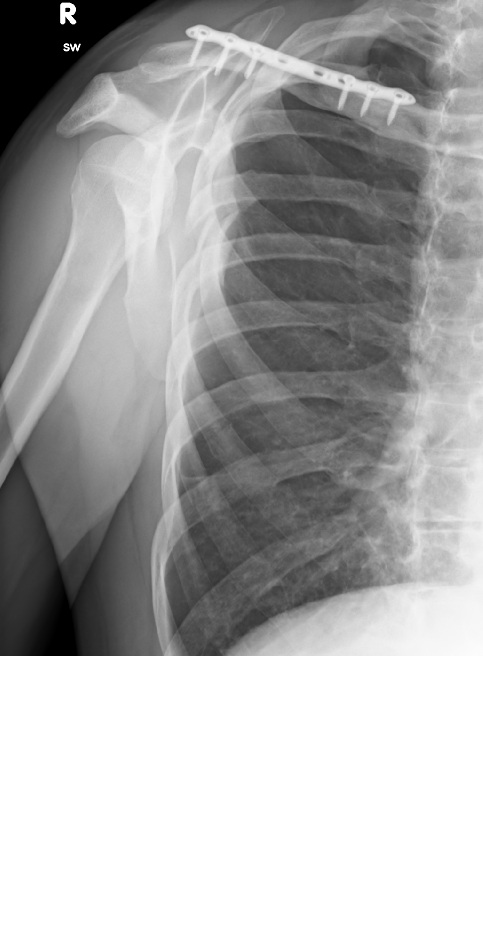

Nächten Tag morgens dann Notaufnahme, röntgen mit Gewicht. Diagnose Rockwood 2. Ansage: 4 Wochen Gilrichst, in 2 Wochen nochmal beim Örtlichen Orthopäden zur Nachsorge vorstellig werden. Soweit so gut.

Dann, hatte ich eine Woche Später noch die Idee zusätzlich zum Bericht der Notaufnahme noch den des Radiologen anzufordern, hier stand dann: Tossy 3. Danach natürlich erstmal Kopfkino, könnte Tossy 3 nicht operiert werden? Was ist der Unterschied? Warum sagen dier in der Notaufnahme was anderes?